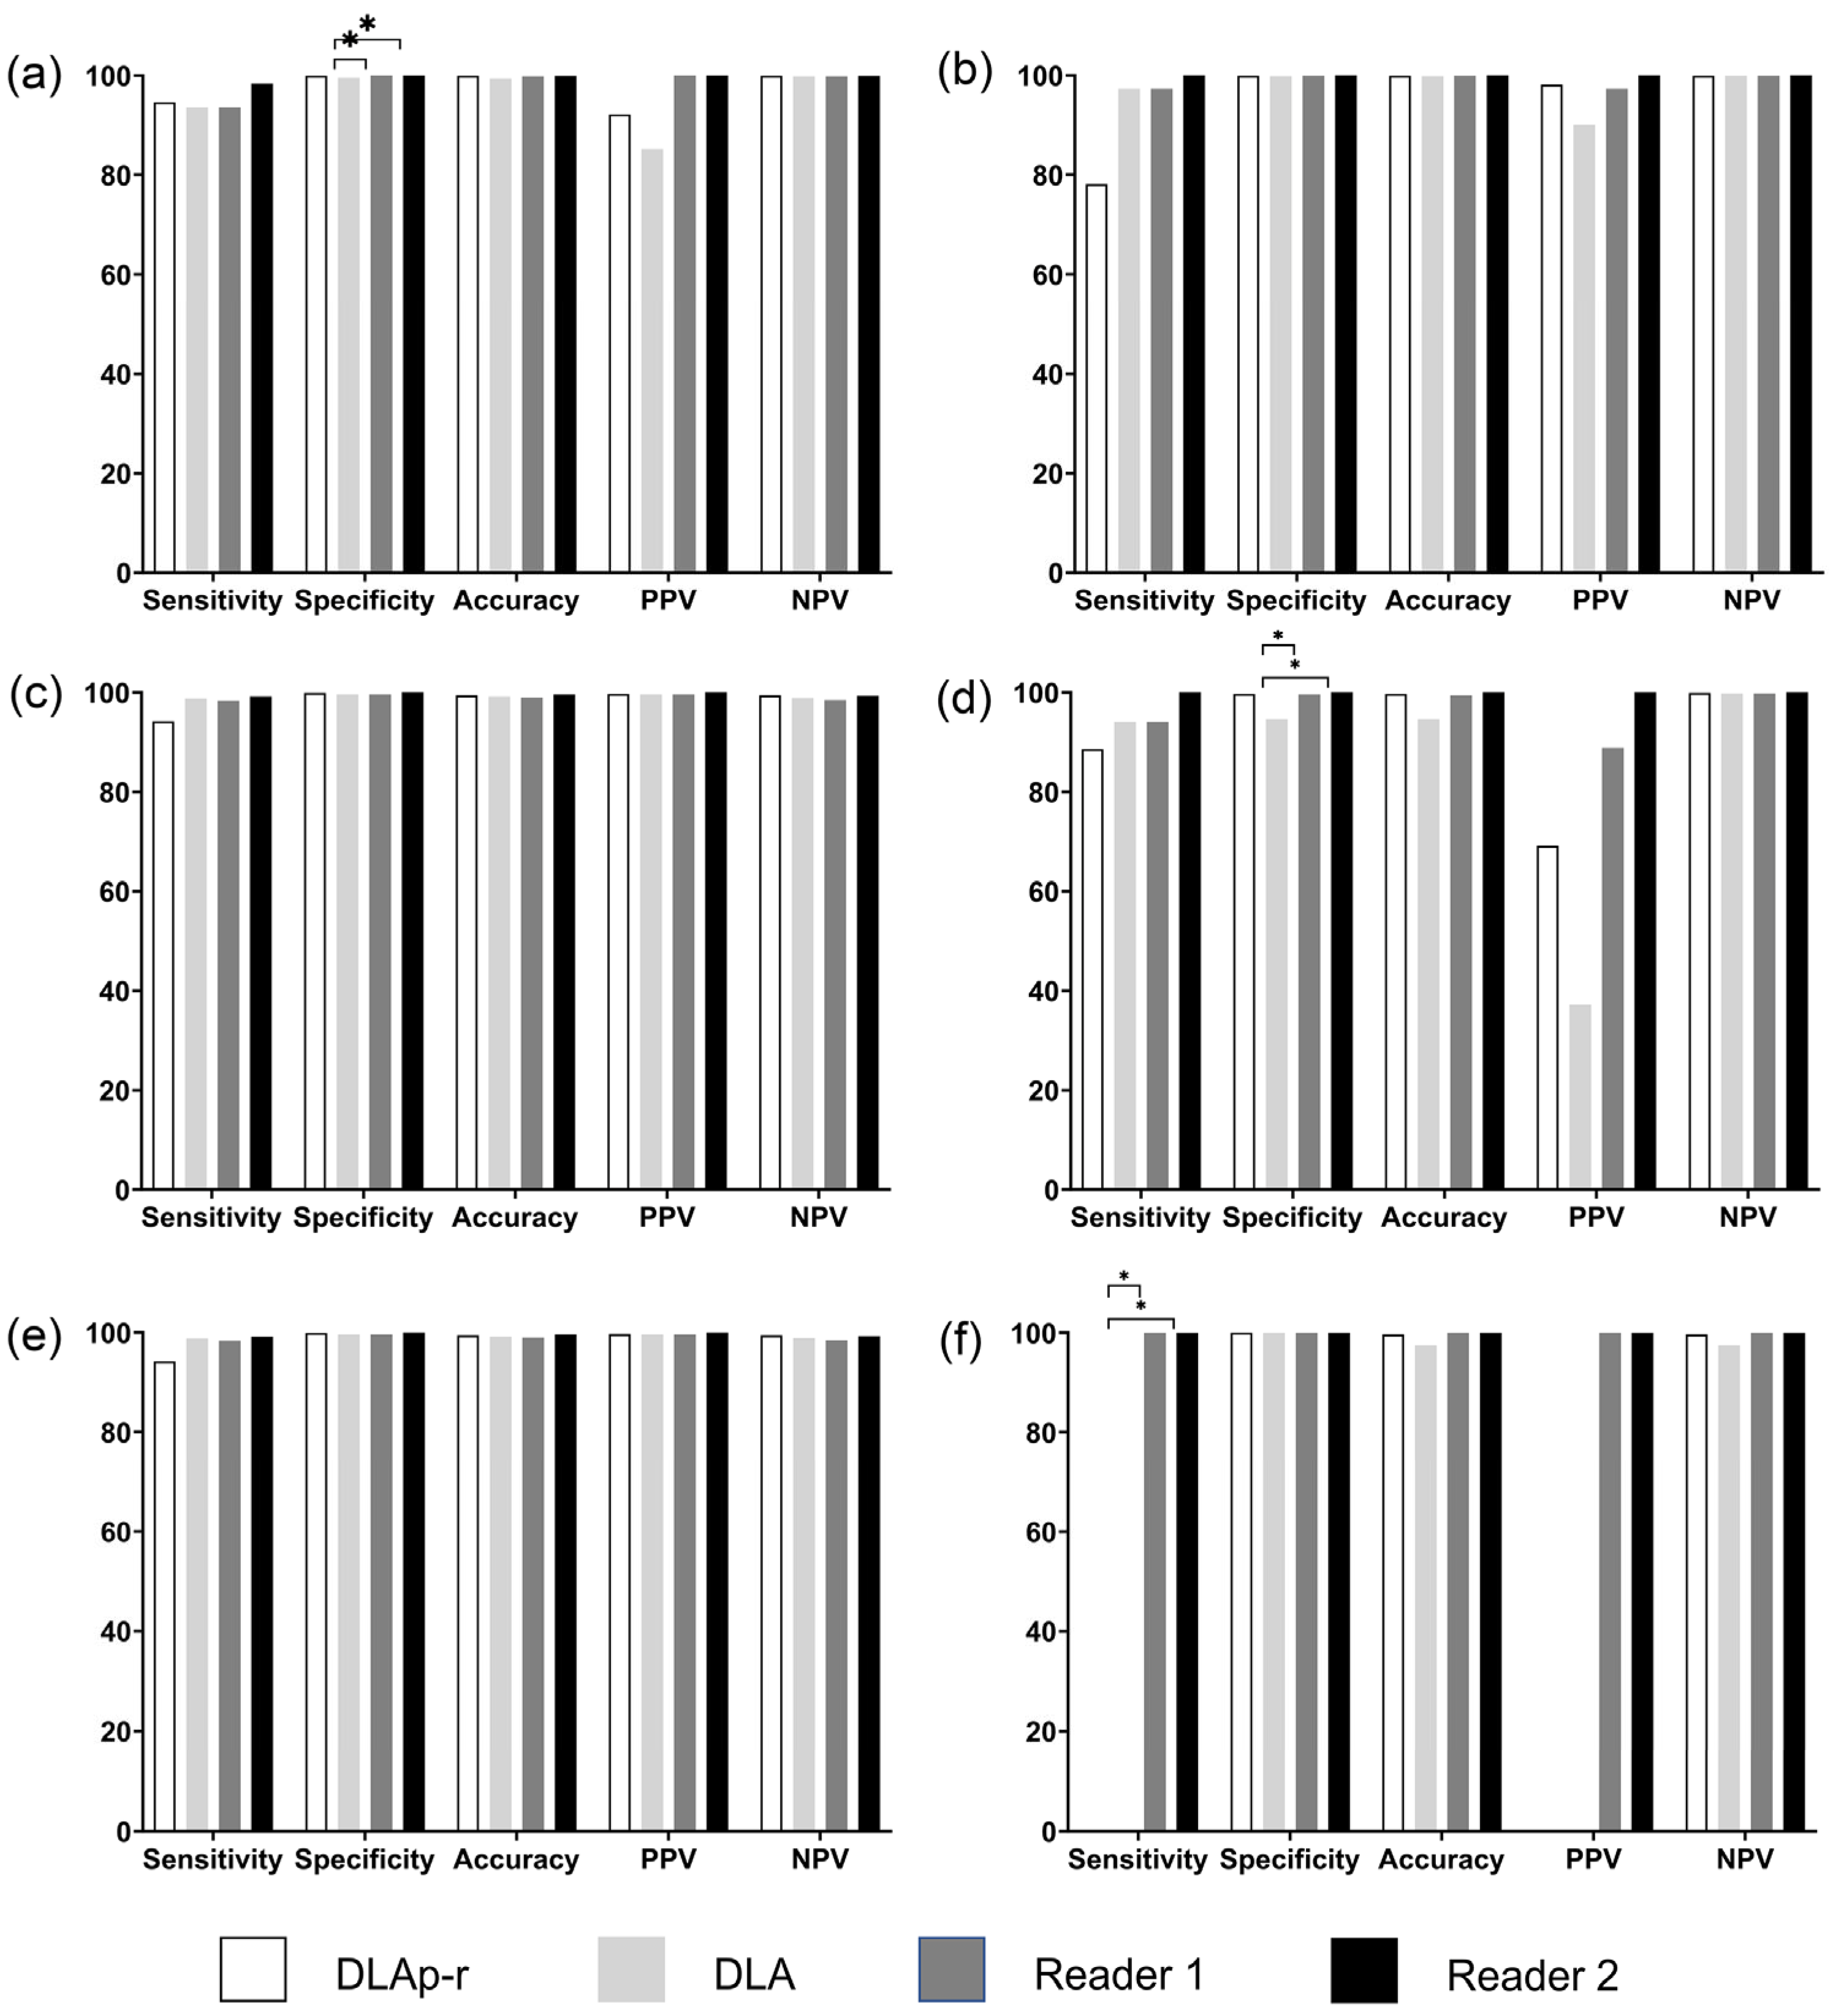

3.2. External Validation on Prototype Software

3.2.2. Abdomen CT AP Tomogram

3.2.3. Spine CT AP and Lateral Topograms

3.2.4. Retrospective Observations for DLA Misclassification